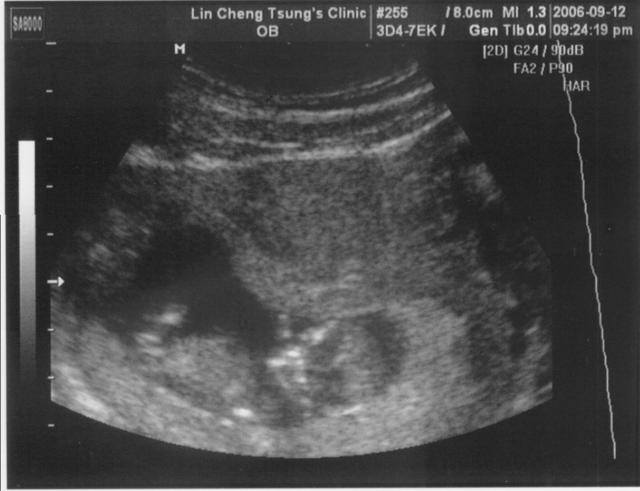

2006.09.12

三個月大